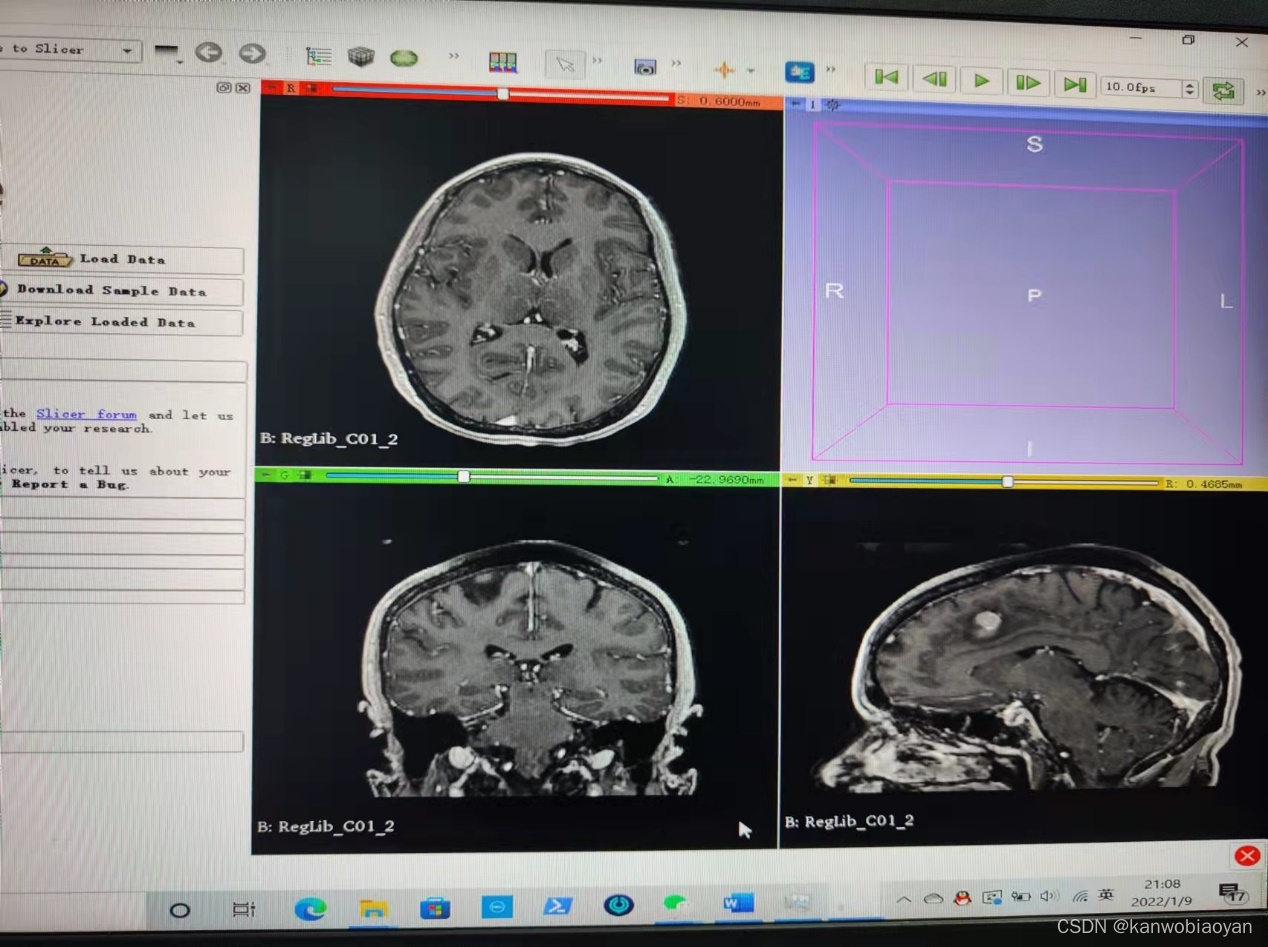

可以通过点击File中的add data来添加我们所收集的数据,以图象的形式呈现

编辑栏中也有许多设置可以对图像及模型进行调节。图像的下方的条可以移动,使得图形的形态发生变化。

在第一象限有一个三维空间,可以供用户使用。

我在输入医学数据后,播放模拟人体组织的运作,颅脑发育,心脏跳动,胸腔呼吸。总的来说,这是一个非常好用的软件,能让我们清晰的看到物体的内部结构。主要使得医生能有效的了解病人器官异常的具体位置。同时,对普通人来说,可以来分析复杂结构的物体。对于那些英语不好的人,也可以用这个软件顺便加强英语能力,岂不美哉。